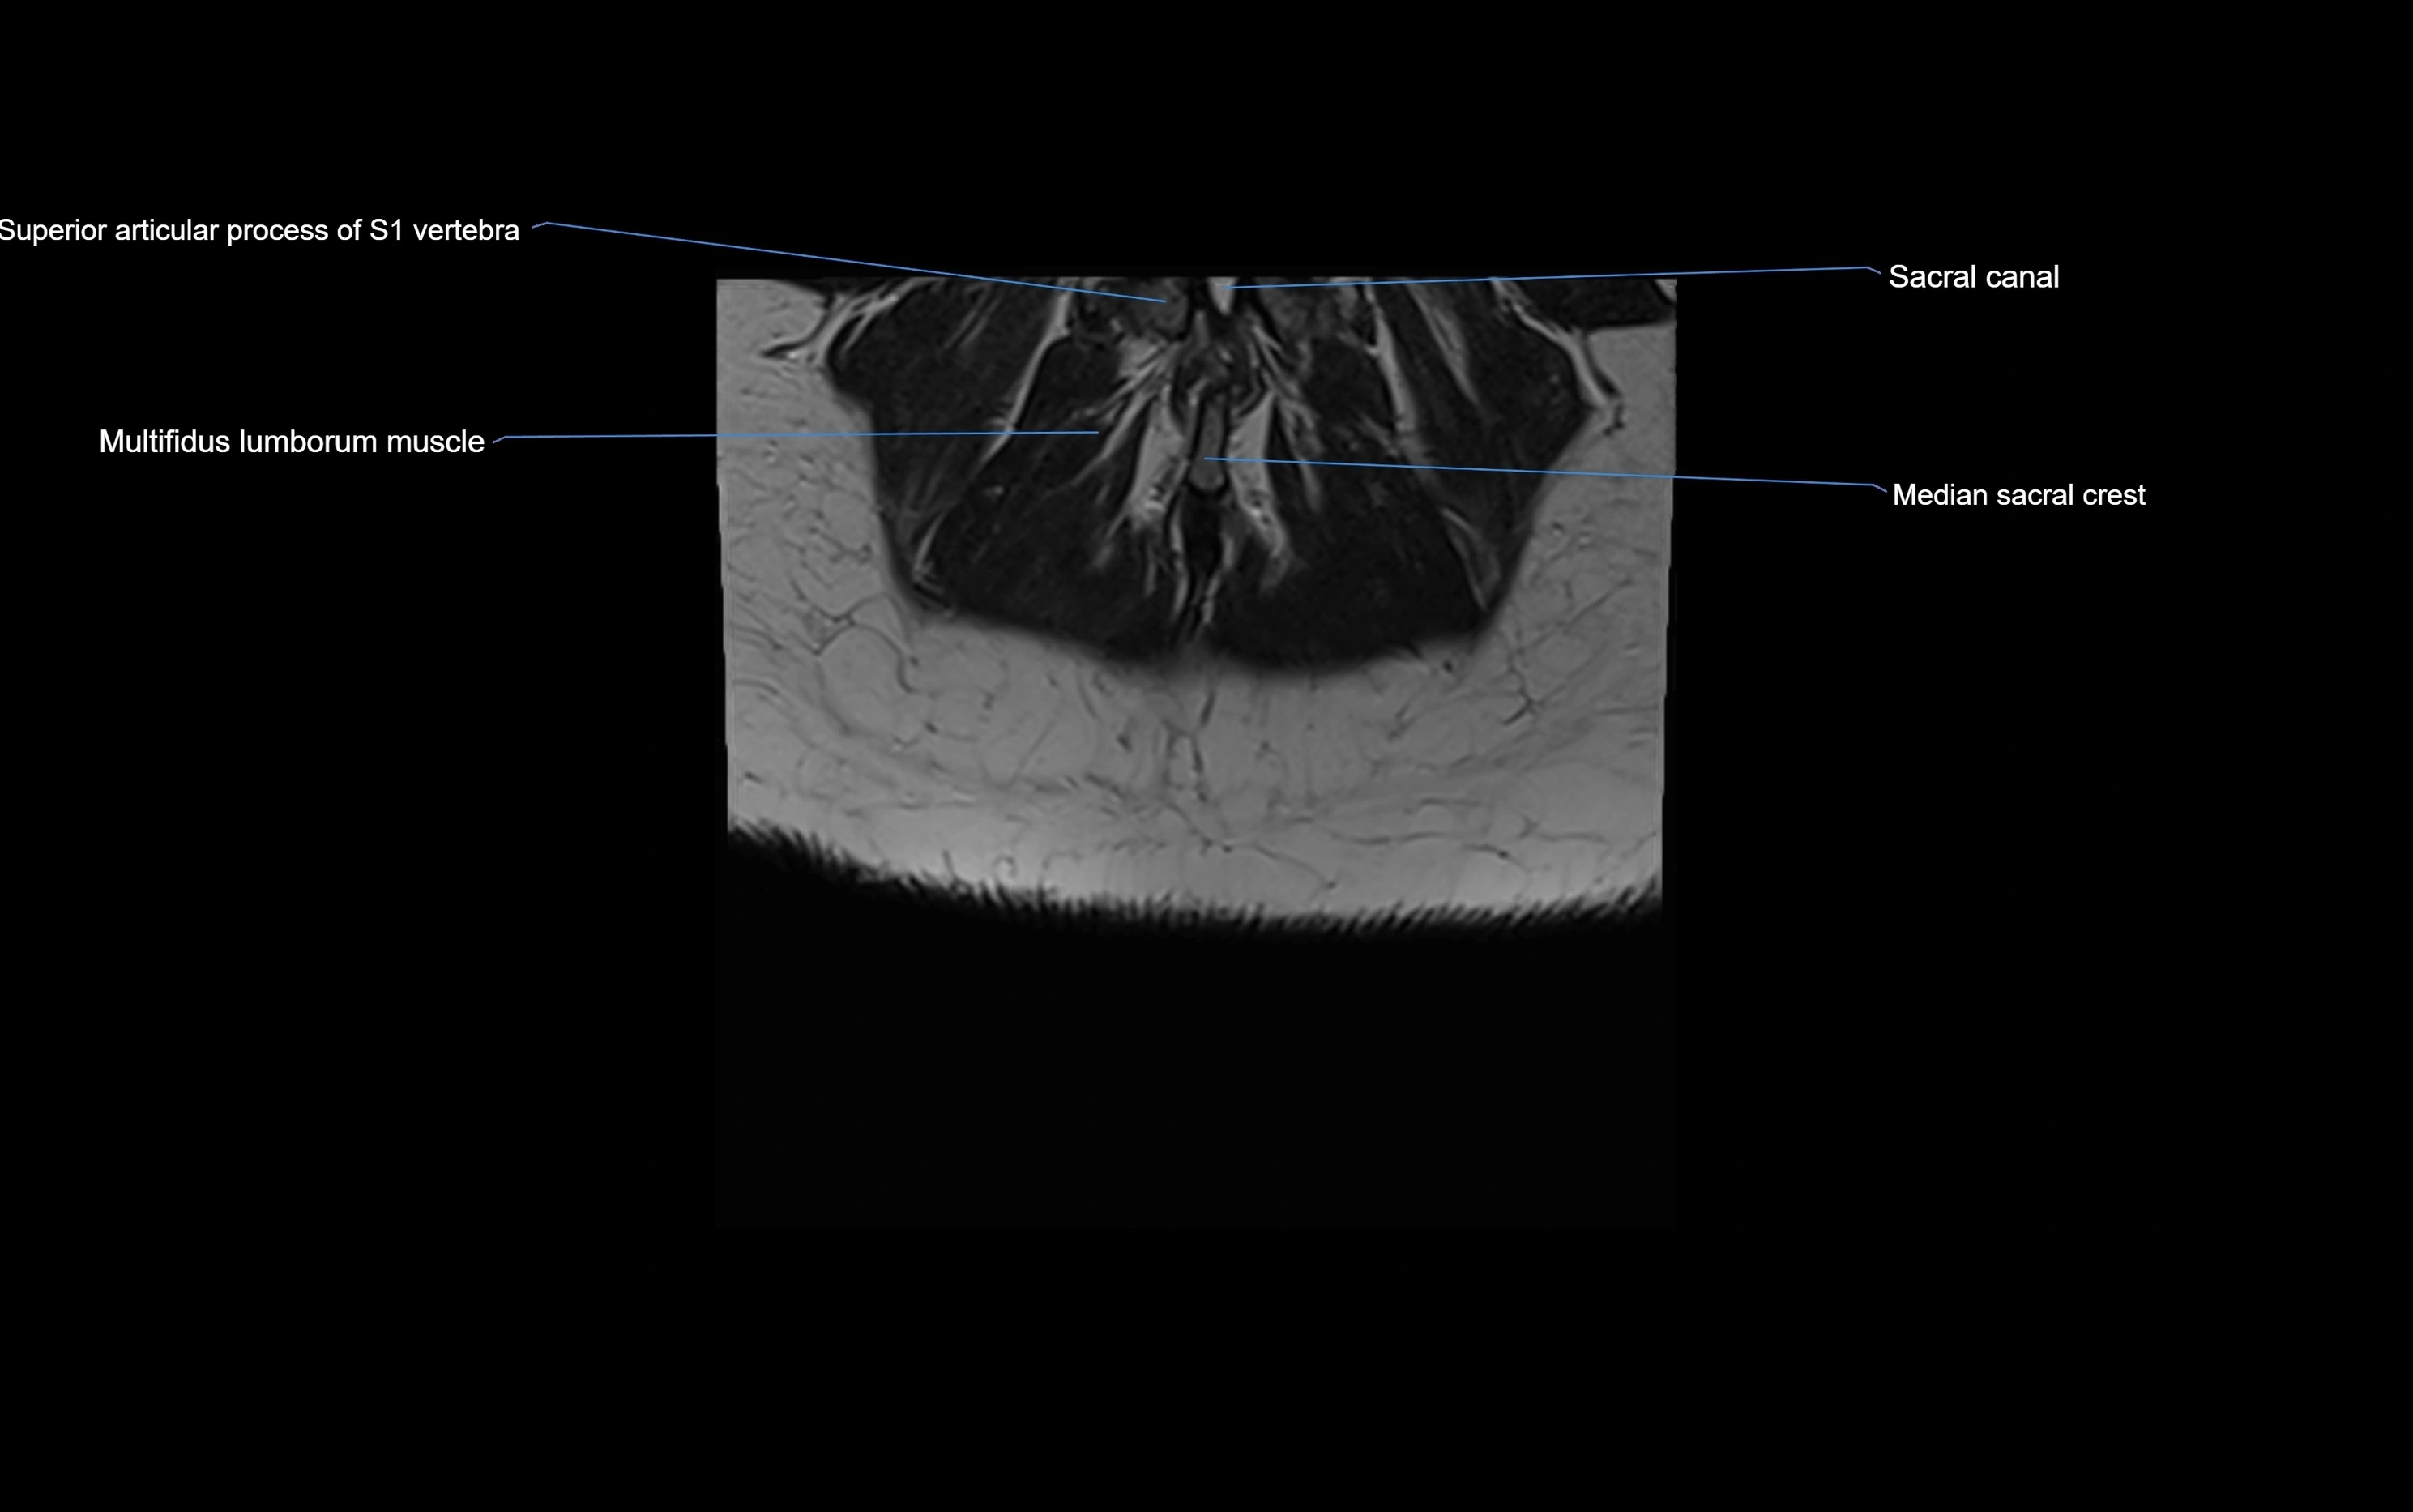

CT image

image